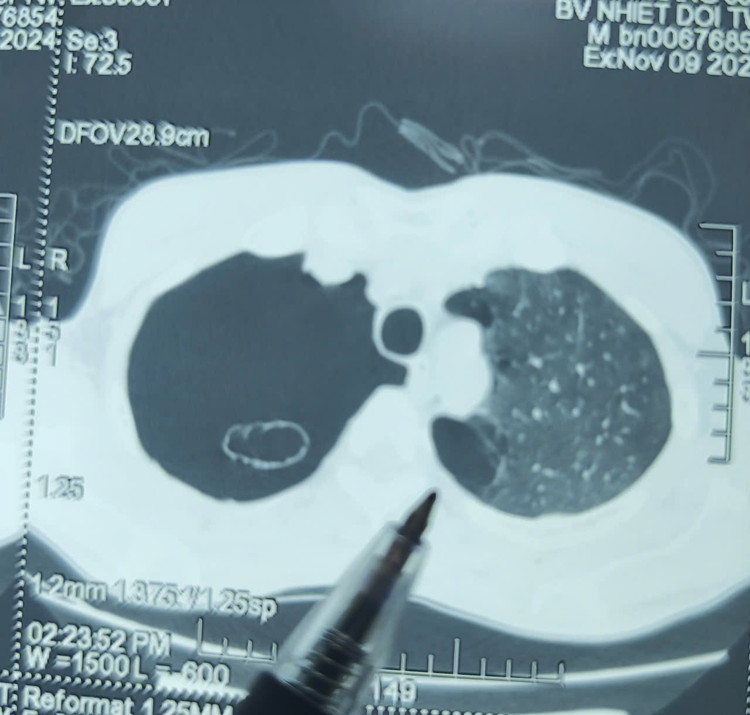

Nhập viện, anh được các bác sĩ chẩn đoán tràn khí màng phổi và được đặt ống dẫn lưu cấp cứu kịp thời, hỗ trợ thở. Sau cấp cứu, anh T được thăm khám toàn diện và phát hiện phổi có nhiều bóng giãn, phế nang có nhiều bóng khí do phổi bị thủng, tràn khí vào màng phổi khiến phổi bị xẹp, không giãn nở được gây khó thở .

| Hình ảnh tràn khí màng phổi trên phim chụp - Ảnh BVCC |